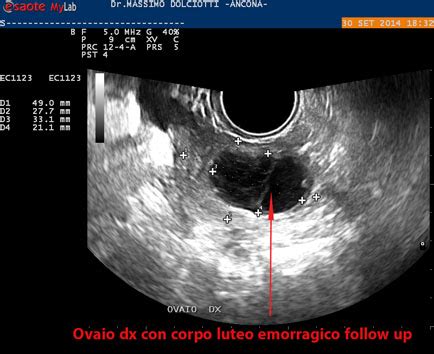

Corpo Luteo Emorragico: Cause e Sintomi

Il corpo luteo emorragico si forma quando, al termine dell'ovulazione, la cavità follicolare viene occupata da un coagulo; quando si accumula una quantità di sangue eccessiva, si può sviluppare un ematoma. Il corpo luteo diviene emorragico quando si accumula un'eccessiva quantità di sangue nella cavità follicolare al termine dell'ovulazione. In alcuni casi, si forma un ematoma che induce ingrossamento ovarico, dolore pelvico acuto e, in caso di rottura, perdita di sangue vaginale e/o intraperitoneale.

- Esame ecografico: L'ecografia (addominale o transvaginale) è fondamentale per visualizzare il corpo luteo emorragico, valutarne le dimensioni e la presenza di eventuali versamenti ematici. È importante anche per la diagnosi differenziale con altre neoformazioni ovariche.

- Diagnosi differenziale: È cruciale distinguere il corpo luteo emorragico da altre condizioni come cisti luteinica, cisti endometriosiche, lesioni neoplastiche, dermoidi e torsione ovarica. Nel caso del Mittelschmerz, è necessario escludere patologie come appendicite, PID, endometriosi e cisti ovariche.